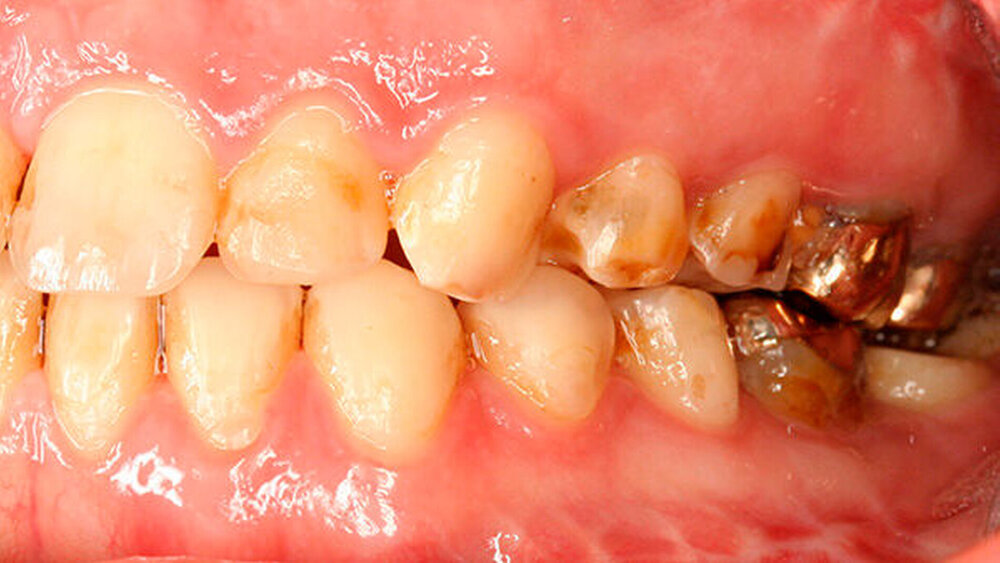

a) Dentinogenesis imperfecta. Da alle Zähne betroffen sind, ist von einer genetisch bedingten Fehlbildung auszugehen. Die Zähne der Patientin weisen zudem eine veränderte Farbe auf. Darüber hinaus sind Abplatzungen des Schmelzes vorzufinden. Trotzdem liegt keine Dentinogenesis imperfecta vor. Die Abplatzungen sind größtenteils geringfügig und zunächst oberflächlich, das heißt nicht unmittelbar bis zum Dentin. Die Farbänderung der Zähne entspricht nicht dem klassischen Bild einer Dentinogenesis imperfecta (siehe auch Abbildungen 3 und 4).

Zudem kann es immer wieder zu Abplatzungen des verbliebenen Schmelzes kommen, so dass der entsprechende Zahn eine neue Restauration benötigt, oder die schon vorhandene ausgedehnt werden muss (siehe auch Abbildungen 1 bis 3) [Crawford et al., 2007].